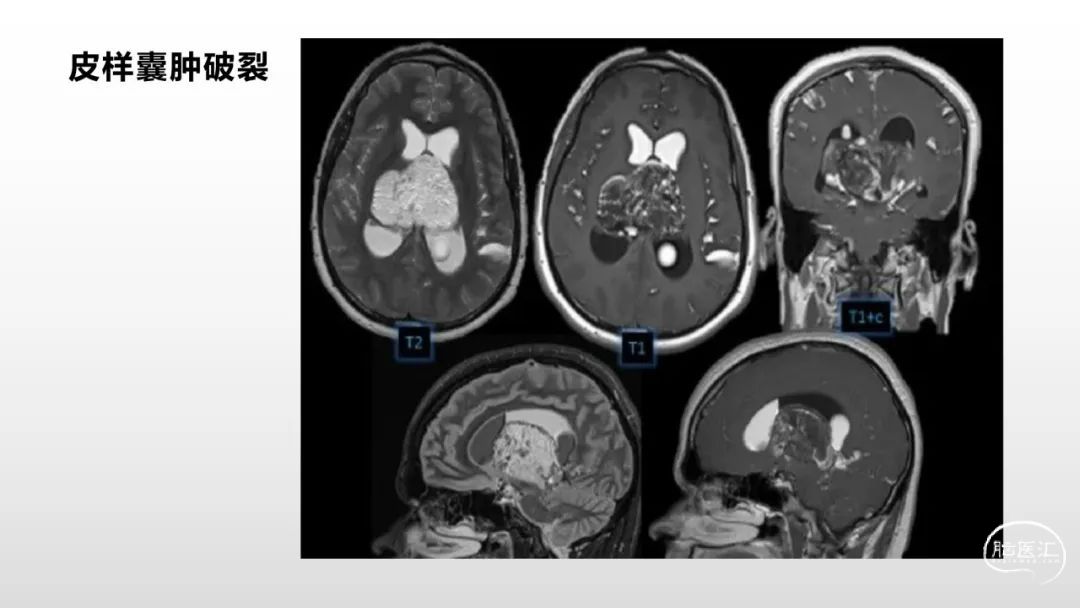

颅脑影像诊断基础知识讲座:脑膜病变